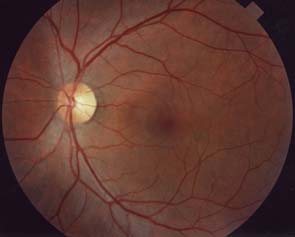

Vrstva nervových vláken

Je tvořena axony gangliových buněk pokrytých astrocyty, probíhajících v kanálcích z výběžků Mullerových buněk ve svazečcích o průměru 20 um. Svazečky jsou morfologickým podkladem jemného žíhání. Světlé proužky mezi tmavými mezerami jsou výběžky Mullerových buněk, ve kterých probíhají nervová vlákna. Temporálně i nasálně je žíhání jemné a každý proužek je tvořen jedním svazečkem vláken. V horním i dolním temporálním kvadrantu je jsou proužky silnější a tím i lépe viditelné, každý proužek má několik svazečků (svazečky jsou v několika vrstvách).

Lokalizovaný výpadek nervových vláken byl popsán poprvé teprve roku 1973 Hoytem. Je vějířovitého tvaru, připomínající ocas komety. Vyskytuje se u 20% glaukomů, není však pro glaukom specifický (drůzy, chorioretinální jizvy, dlouho trvající edém disku, pozánětlivá atrofie). Není u zdravých očí.

U glaukomu bývá v časných a středních stádiích, častěji u fokláního ischemického typu, v místech, kde byly před více než 2 měsíci peripapilární hemorhagie, kde exkavace je protažena k okraji terče a kde je rozsáhlejší peripapilární atrofie. Nebývá u pokročilého glaukomu. Airaksinen: výpadky předcházejí perimetrickým změnám.

Při progresi glaukomu nejprve bývají poškozeny gangliové buňky v blízkosti temporálního švu sítnice. Jejich axony probíhají v hlubší vrstvě nervových vláken a do zrakového nervu pronikají v jeho periferii. Protože vzniklý defekt je překryt dalšími povrchnějšími vrstvami, výpadek není při pozorování sítnice zřetelný. Až po ztrátě poloviny vrstvy nervových vláken se defekt stává zřetelným oftalmoskopicky.

Difusní výpadek nervových vláken vzniká při více méně rovnoměrném úbytku gangliových buněk a jejich vláken po celé sítnici. Zrakový nerv mívá koncentrickou exkavaci a plocha neuroretinálního lemu bývá úzká. Klinicky se tento výpadek nejlépe pozná při pohledu na cévy, které jsou kryty jen vnitřní limitující membránou a při pohledu přímým oftalmoskopem mají na první pohled nezvykle ostré hranice, jakoby vystupovaly nad povrch sítnice.

Technika vyšetření vrstvy nervových vláken

Pomůcky: štěrbinová lampa, 90 D čočka a fixační světélko na protější straně místnosti.

Nastavení lampy: zelené světlo paralelně s osou našeho pohledu, paprsek co nejvíce vertikálně protažený, aby pokryl oblast horních i dolním temporálních nervových svazečků. Zaostříme na terč tak, abychom ho viděli prostorově.

Pohybem štěrbinové lampy pak světelný proužek posuneme mezi terč a foveolou. Pohledem srovnáváme žíhání sítnice směrem dovnitř od velkých cévních kmenů, srovnáváme rozdíl mezi horními a dolními svazky vláken. U zdravého oka bývá žíhání a zastření cévních kmenů směřujících do makuly výraznější v dolní polovině sítnice než v horní.